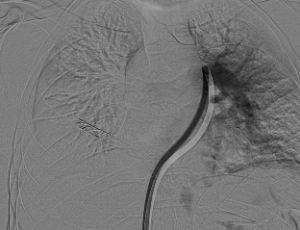

سجل مجمع الدمام الطبي أحد مكونات تجمع الشرقية الصحي ، إنجازاً طبياً نوعياً بعد نجاح فريق الأشعة التداخلية في إنقاذ حياة مريض كان يعاني من جلطة رئوية حادة وكبيرة شكّلت خطراً مباشراً على حياته ، وذلك باستخدام تقنية طبية متقدمة دون الحاجة إلى جراحة قلب مفتوح .

وكان المريض قد نُقل بشكل إسعافي من أحد المستشفيات وهو في حالة حرجة ، نتيجة معاناته من ضيق شديد في التنفس وانخفاض حاد في مستوى الأكسجين ، إثر انسداد كامل في الشريان الرئوي الرئيسي بسبب خثرات وريدية عميقة ظهرت بعد خضوعه لعملية منظار لمفصل الركبة.

وبفضل سرعة الاستجابة وجاهزية فريق الأشعة التداخلية جرى التدخل العلاجي العاجل وفتح الشريان الرئوي وسحب الجلطة بالكامل بدقة عالية ، ما أدى إلى تحسّن فوري في العلامات الحيوية واستقرار الحالة دون تسجيل أي مضاعفات.